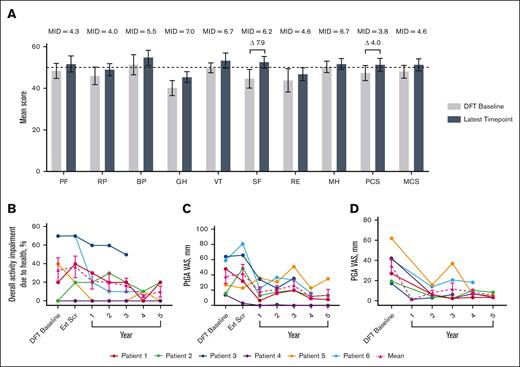

Short-Form Health Survey 36 mean physical component score increased by 4.0 points and social functioning by 7.9 at year 5, both of which are considered clinically meaningful improvements (Figure 1).25 Mean overall activity impairment because of health, as assessed via the Work Productivity and Activity Impairment plus Classroom Impairment Questionnaire, reduced by 70.0%. Patient and physician general assessments showed reductions in mean disease activity of 63.2% and 86.3%, respectively.

Changes in HRQoL over time. (A) Normed subscale and component scores from the SF-36 survey, with higher scores indicating greater HRQoL.26 MIDs for patients with IEI are from the literature.25 The latest time point for P1, P2, P3, P4, P5, and P6 are as follows: year 5, 5, 3, 5, 5, and 4, respectively. Differences in scores between DFT baseline and latest time point that exceed MIDs are illustrated with a delta symbol (Δ) followed by the value of the difference. Dotted line indicates general US population average. (B) Individual and mean WPAI-CIQ overall activity impairment because of health scores over time, with lower scores indicating less impairment because of health. n values for DFT baseline, Ext Scr and years 1, 2, 3, 4, and 5 are as follows: 6, 6, 6, 6, 6, 5, and 4, respectively. (C) Individual and mean patient general assessment scores are shown with lower scores indicating a reduction in disease activity. n values for DFT baseline, Ext Scr and years 1, 2, 3, 4, and 5 are as follows: 6, 6, 6, 6, 6, 5, and 4, respectively. (D) Individual and mean physician general assessment scores are shown with lower scores indicating a reduction in disease activity. There were no values reported for Ext Scr. n values for DFT baseline and years 1, 2, 3, 4, and 5 are as follows: 6, 1, 6, 6, 5, and 4, respectively. Error bars are standard error of the mean. BP, bodily pain; Ext Scr, extension screening; GH, general health; MCS, mental component score; MH, mental health; MID, minimally important difference; PCS, physical component score; PF, physical functioning; PGA, physician general assessment; PtGA, patient general assessment; RE, role (emotional); RP, role (physical); SF-36, Short-Form Health Survey 36; SF, social functioning; VT, vitality; WPAI-CIQ, Work Productivity and Activity Impairment Questionnaire plus Classroom Impairment Questionnaire.

Changes in HRQoL over time. (A) Normed subscale and component scores from the SF-36 survey, with higher scores indicating greater HRQoL.26 MIDs for patients with IEI are from the literature.25 The latest time point for P1, P2, P3, P4, P5, and P6 are as follows: year 5, 5, 3, 5, 5, and 4, respectively. Differences in scores between DFT baseline and latest time point that exceed MIDs are illustrated with a delta symbol (Δ) followed by the value of the difference. Dotted line indicates general US population average. (B) Individual and mean WPAI-CIQ overall activity impairment because of health scores over time, with lower scores indicating less impairment because of health. n values for DFT baseline, Ext Scr and years 1, 2, 3, 4, and 5 are as follows: 6, 6, 6, 6, 6, 5, and 4, respectively. (C) Individual and mean patient general assessment scores are shown with lower scores indicating a reduction in disease activity. n values for DFT baseline, Ext Scr and years 1, 2, 3, 4, and 5 are as follows: 6, 6, 6, 6, 6, 5, and 4, respectively. (D) Individual and mean physician general assessment scores are shown with lower scores indicating a reduction in disease activity. There were no values reported for Ext Scr. n values for DFT baseline and years 1, 2, 3, 4, and 5 are as follows: 6, 1, 6, 6, 5, and 4, respectively. Error bars are standard error of the mean. BP, bodily pain; Ext Scr, extension screening; GH, general health; MCS, mental component score; MH, mental health; MID, minimally important difference; PCS, physical component score; PF, physical functioning; PGA, physician general assessment; PtGA, patient general assessment; RE, role (emotional); RP, role (physical); SF-36, Short-Form Health Survey 36; SF, social functioning; VT, vitality; WPAI-CIQ, Work Productivity and Activity Impairment Questionnaire plus Classroom Impairment Questionnaire.